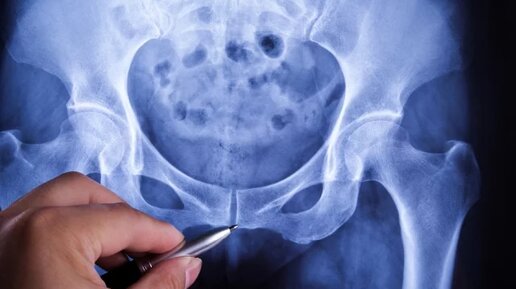

Где находится копчик? 🤔 Многие считают этот отдел бесполезным, но на самом деле копчик выполняет ряд важных функций, обеспечивая опору и участвуя в работе мышц тазового дна. 🤔 Что такое копчик? 🤔 Копчик или копчиковая кость (от латинского «os coccygis») — это нижний отдел позвоночного столба, состоящий из 3-5 сросшихся позвонков. 🤔Он представляет собой небольшую кость треугольной формы, расположенную в самом конце позвоночника.🙈 Этимология слова «копчик» связана с его формой, напоминающей клюв птицы.🫂 Слово происходит от древнегреческого κόκκυξ (kokkyx), что в переводе означает «кукушка» или «клюв кукушки».❤ Для чего нужен копчик и где он находится?🤔 Хотя копчик состоит из рудиментарных — не до конца развитых — позвонков, он выполняет несколько важных функций, необходимых для нормальной жизнедеятельности. 🤔Где именно расположена эта костная часть и действительно ли она нужна организму, — рассказала aif.ru врач-терапевт Альбина Ханбабаева.❤ Копчик играет крайне важную роль в организме: он является своего рода точкой опоры для позвоночного столба. ❤Кроме того, копчик обеспечивает нормальное функционирование органов малого таза, поскольку к нему прикрепляются связки, удерживающие в правильном положении прямую кишку, органы мочеполовой системы, а также мышцы тазового дна.🤔 Расположен он в нижнем отделе позвоночника, под крестцом, между ягодичными мышцами.🫂 При боли в этой области нужно срочно обращаться к неврологу или травматологу-ортопеду», — предупредил эксперт.🙈 Кроме того, при сидении нижний отдел позвоночника принимает часть нагрузки на себя, помогая равномерно распределить вес тела.🙈 Во избежание кокцигодинии — состояния, которое характеризуется болью в области копчика — врач-терапевт советует не откладывать визит к специалисту, а также больше двигаться и избегать длительного сидения на твердых поверхностях.🫂